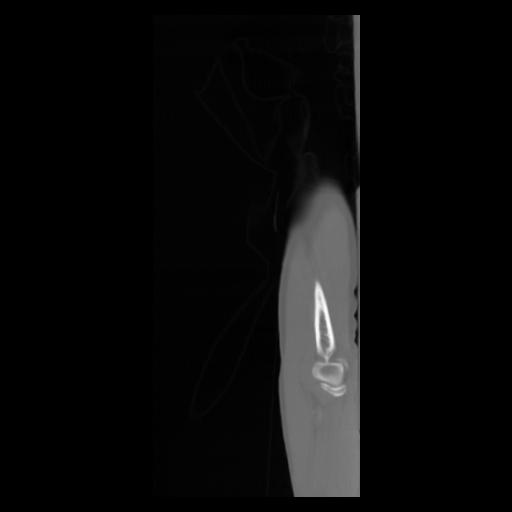

30 CUERPO,CE,Sagittal,3.000,CUERPO,Sagittal,